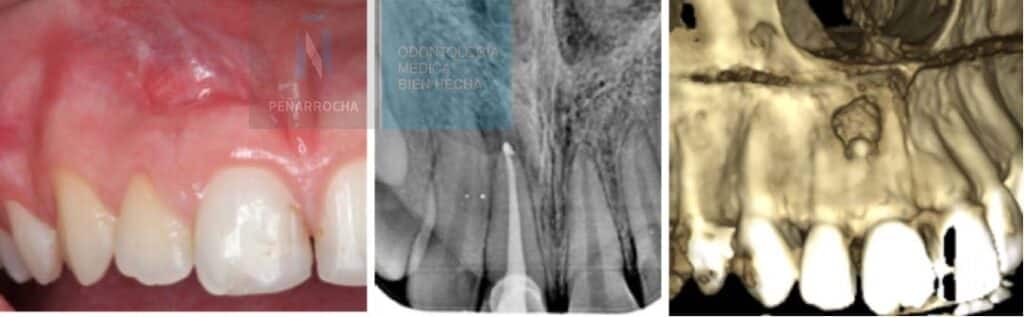

Have you recently undergone a root canal treatment but feel that something is not quite right? A root canal is performed to save a tooth that has been severely damaged by decay or infection. While modern endodontic procedures are highly effective, studies estimate that root canal failure still occurs in about 2% to 16% of […]